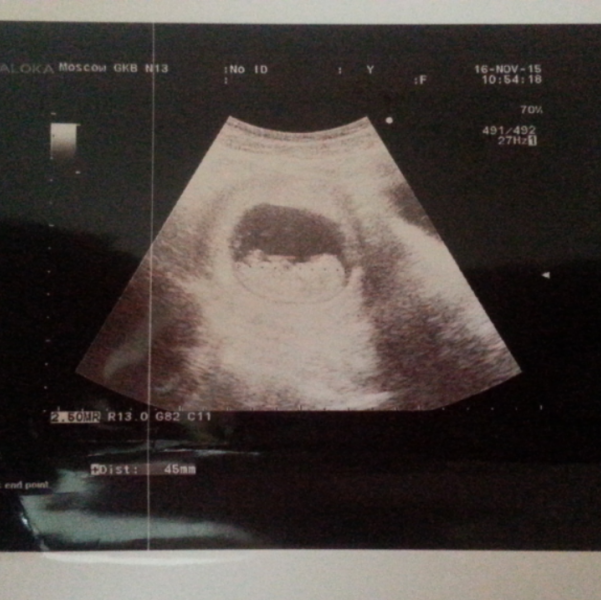

Хоть что-то приятное от лежания на сохранении! Пришел врач, отрезал фото от вчерашнего узи и отдал на память)))))) Девчонки, мы с лаймиком завтра выписываемся, я так счастлива!

@zannochka у меня первое))) поэтому я счастлива! Фоторамку сделаю для узи))))

Фото на память это здорово))) я уже столько насобирала)))😇😇😇